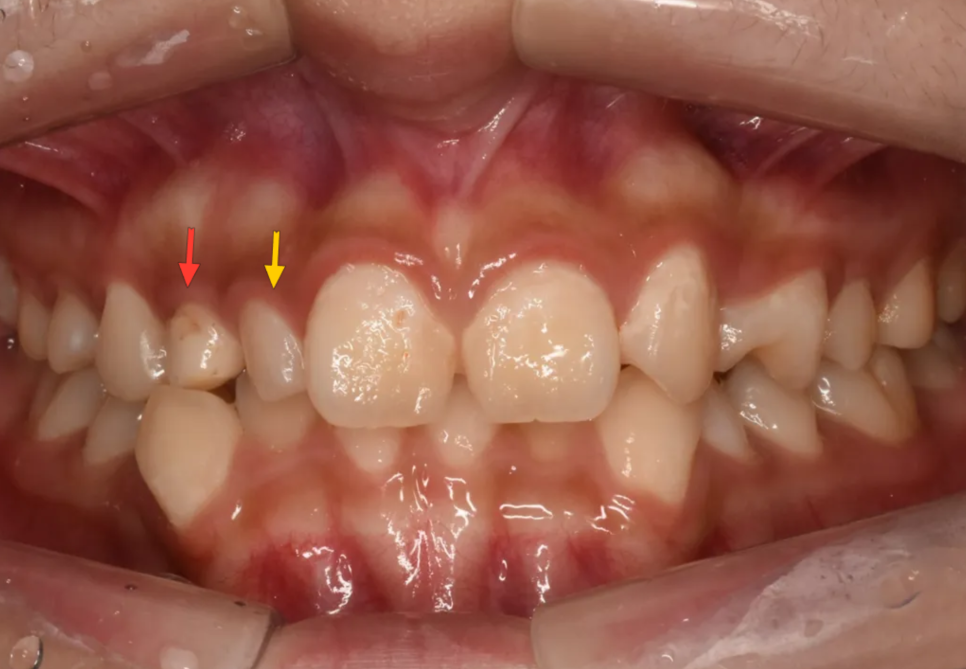

첫번째로 가장 눈에 띄는 것은 사이즈가 유난히 작은 치아들이 존재하는 것입니다. 아래 그림에서 붉은색 화살표는 초등학교때 빠졌어야 할 유치(젖니)가 빠지지 않고 아직 남아있는 경우(유치잔존)입니다. 그래서 다른 치아들(영구치)보다 크기가 작은 것입니다. 노란색 화살표는 선천적으로 이가 작게 태어나는 "왜소치"인 경우입니다.

여기서 젖니가 아직까지 남아있는 이유는, 영구치 송곳니가 매복되어 있어 나오지 못했기 때문입니다. 이는 엑스레이를 찍어보면 깊이 묻혀있는 송곳니를 보면 알 수 있습니다.